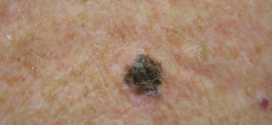

El melanoma maligno. Es una neoplasia originada en el melanocito y su localización más frecuente es la piel. Existen cuatro formas comunes de melanoma maligno (MM) y varias formas infrecuentes. Dentro de las primeras se encuentran: el lentigo maligno, el melanoma extensivo superficial, el melanoma acrolentiginoso y el melanoma nodular, y dentro de las últimas encontramos al melanoma desmoplásica, al …

El melanoma juvenil de Spitz. O nevo, nevus de Spitz. Los nevus o melanoma juvenil son tumores o lesiones benignos del sistema melanocítico. Son lesiones cuya importancia viene determinada por su semejanza histológica con los melanomas. El melanoma juvenil o nevó de Spitz es una rara forma de nevó melanocítico benigno que puede ser confundido fácilmente, no sólo con un …

Leer MásMELANOSIS DE DUBREUILH